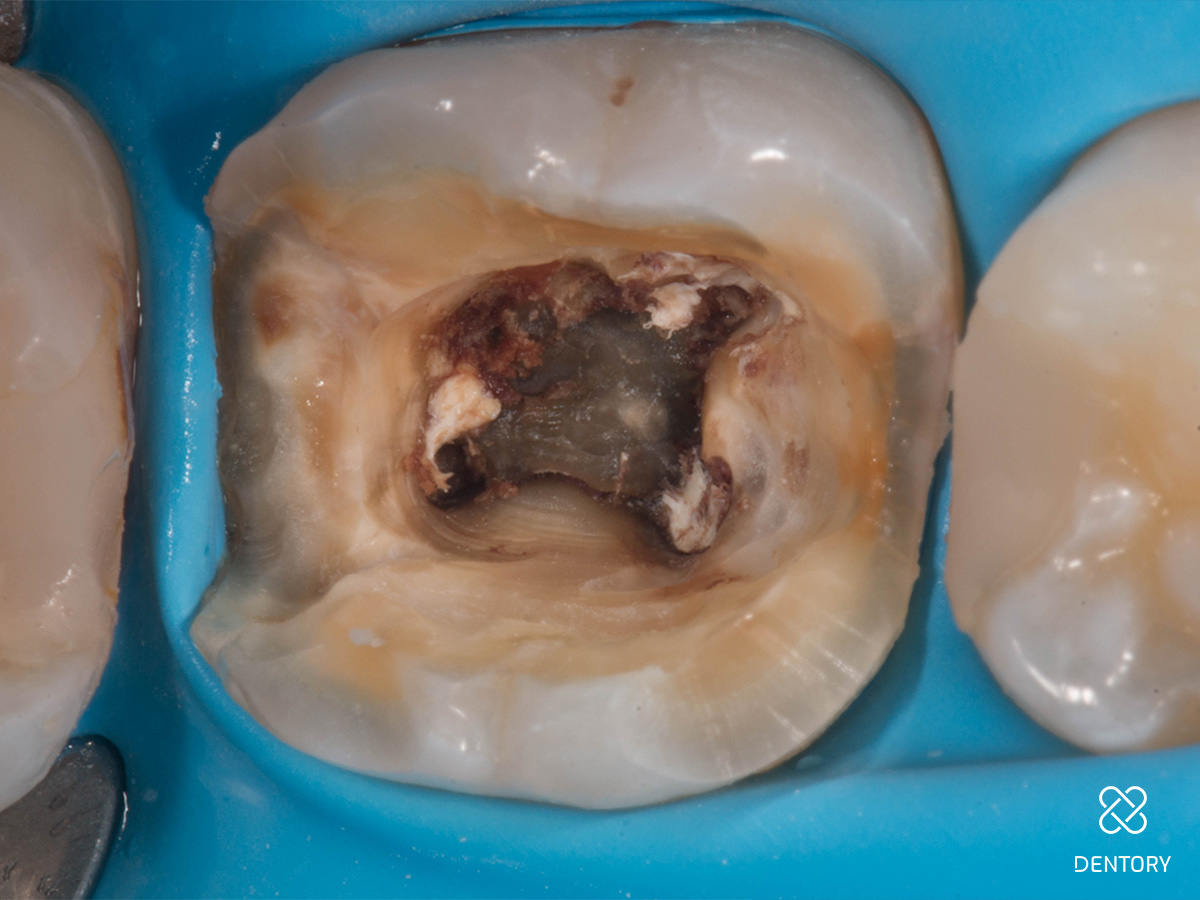

Abbildung 1

Ausgangssituation: Das initiale Röntgenbild zeigt den Grund für die Schwellung.

Abbildung 2

Entfernung der insuffizienten Füllung. Man kann erkennen, dass die Guttapercha aufgrund der hohen Transluzenz des damals verwendeten Materials durch die Füllung scheint.